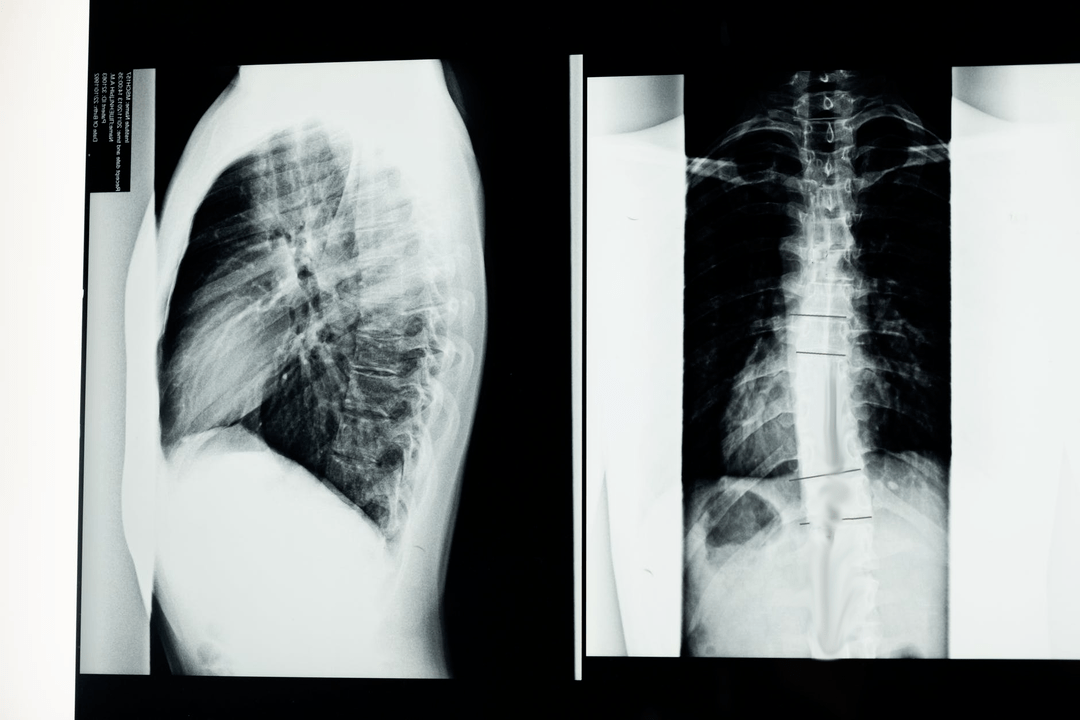

Diagnostiko-azterketak hasi aurretik, neurologoak gaixoaren historia medikoa biltzen du eta bere kexak arretaz aztertzen ditu. Osteokondrosia beste gaixotasun batzuekin sintoma arruntak ditu, beraz, garrantzitsua da patologiak bereizteko gai izatea. X izpien ikerketek osteokondrosiaren diagnostikoa baieztatzen lagunduko dute: erradiografia, mielografia eta tomografia konputazionatua.

Inkestaren X izpi batek bizkarrezurra edo haren atal baten X izpien irudia lortzeko aukera ematen du. Modu honetan, medikuak gaixotasunak kaltetutako kokapena zehaztu dezake. Argitasunerako, X izpien bidez osteokondrosia nola zehazten den azalduko dugu: irudiak orno arteko diskoaren estutzea, hezur-hazkundeak (osteofitoak) edo bizkarrezur-segmentuaren formaren aldaketa erakutsiko ditu.